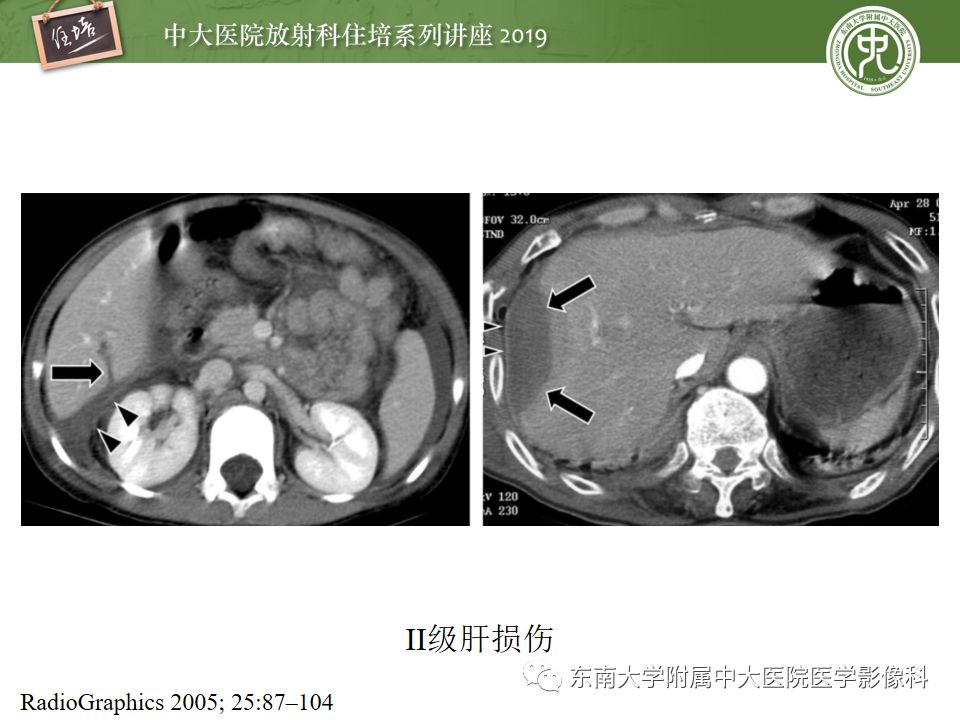

腹腔实性脏器钝性外伤影像诊断